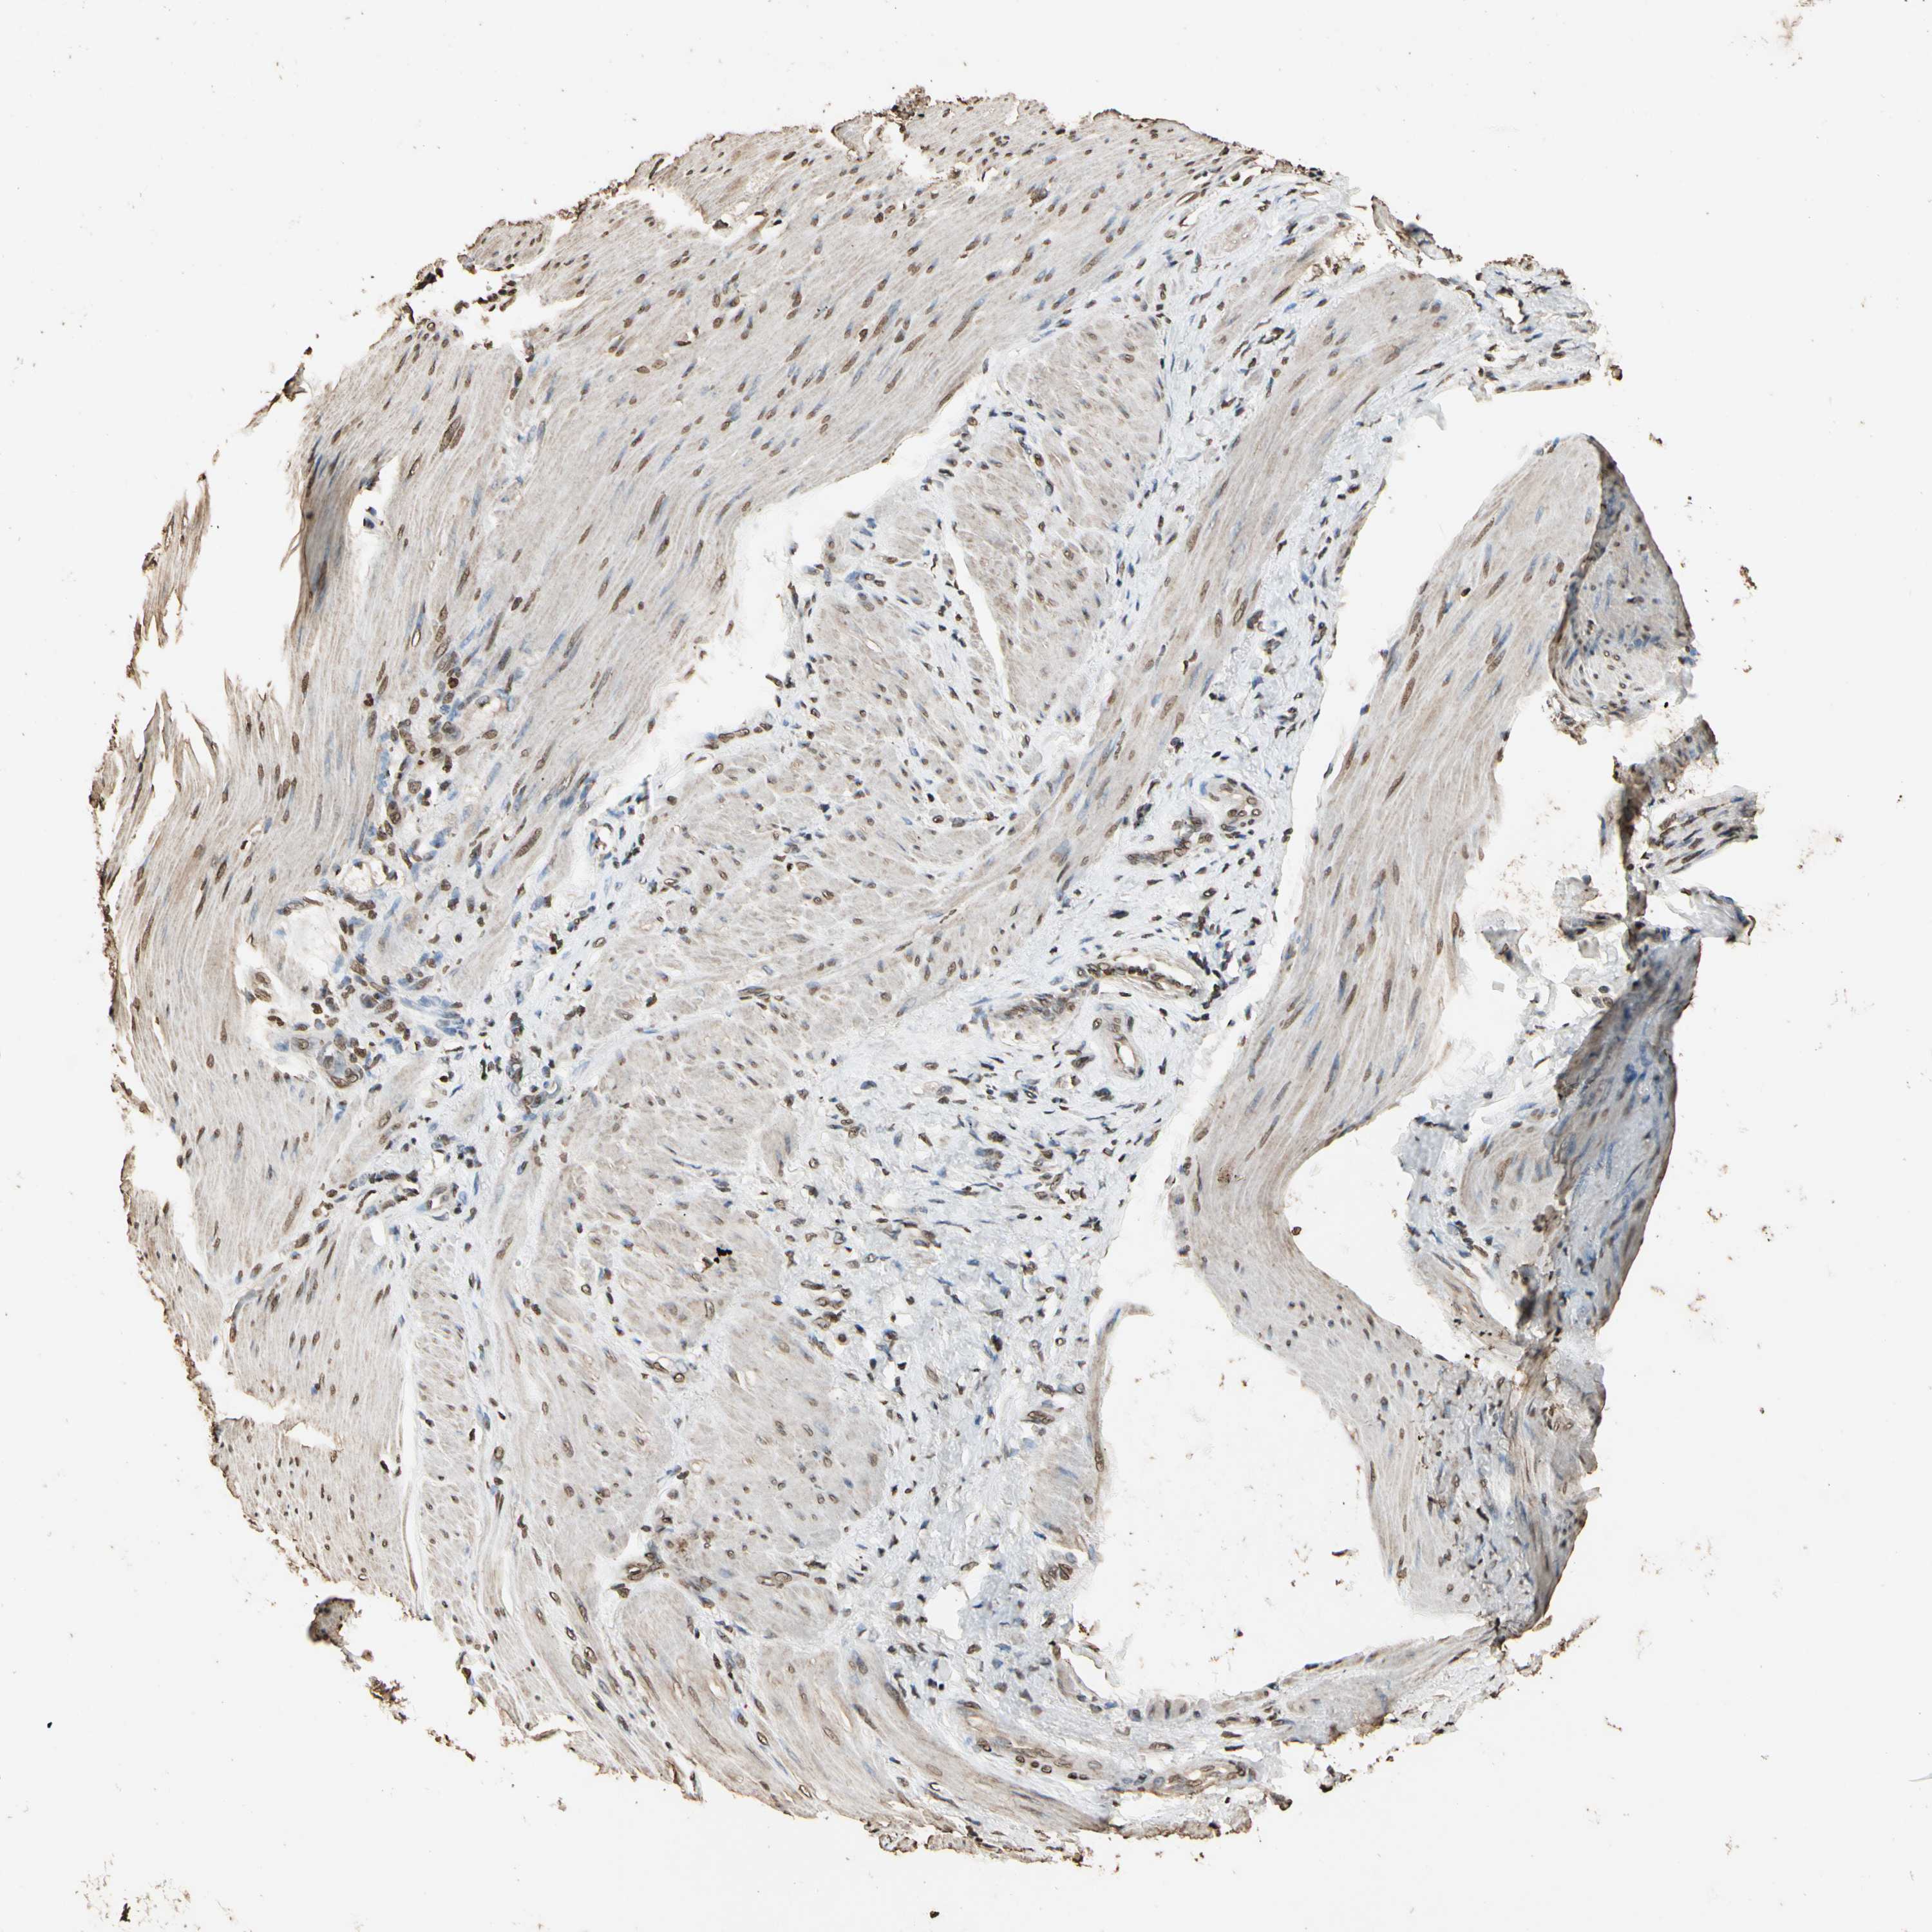

STOMACH CANCER - Protein expressioni

A mouse-over function shows sample information and annotation data. Click on an image to view it in a full screen mode. Samples can be filtered based on level of antibody staining by selecting one or several of the following categories: high, medium, low and not detected. The assay and annotation is described here.

Note that samples used for immunohistochemistry by the Human Protein Atlas do not correspond to samples in the TCGA dataset.

Antibody stainingi

Antibody staining in the annotated cell types in the current human tissue is reported as not detected, low, medium, or high, based on conventional immunohistochemistry profiling in selected tissues. This score is based on the combination of the staining intensity and fraction of stained cells.

Each image is clickable and will lead to virtual microscopy that enables deeper exploration of all samples and also displays staining intensity scores, fraction scores and subcellular localization as well as patient and tissue information for each sample.

Antibody HPA019039

Antibody CAB009058

Staining

High

Medium

Low

Not detected

Intensity

Strong

Moderate

Weak

Negative

Quantity

>75%

75%-25%

<25%

None

Location

Nuclear

Cytoplasmic/membranous

Cytoplasmic/membranous,nuclear

Adenocarcinoma, NOS